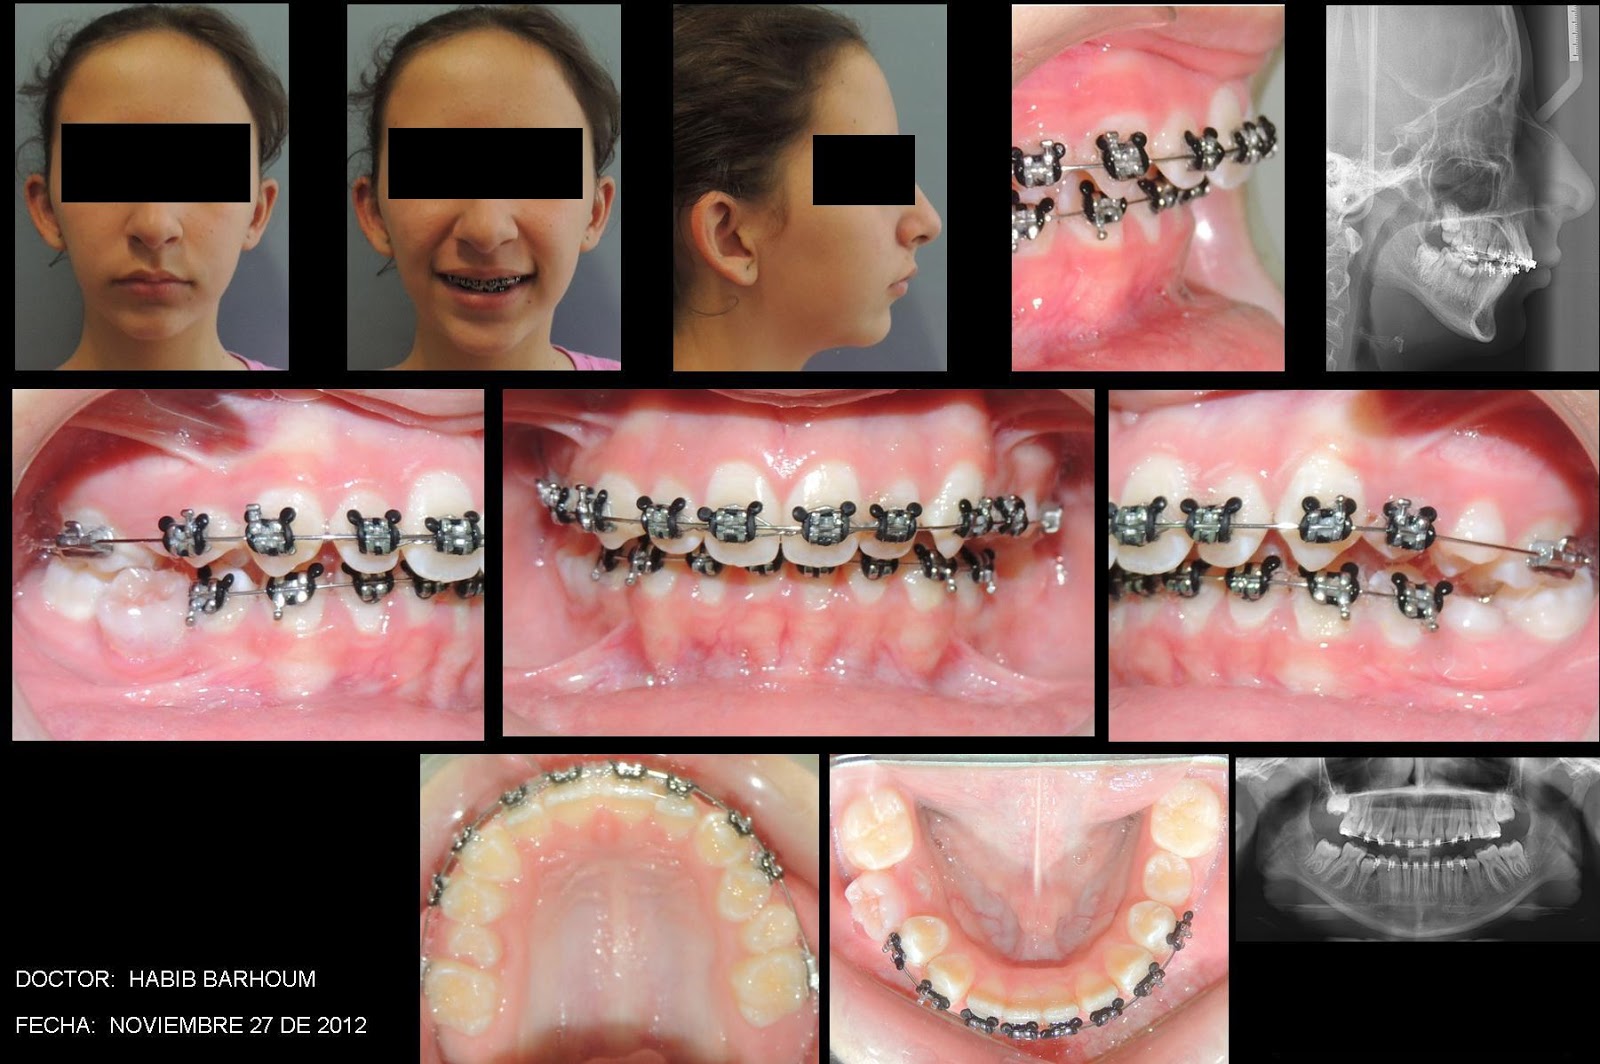

ESTE ES EL CASO DE UNA PACIENTE QUE CONSULTA POR TENER UNA MANDÍBULA CORTA QUE PODRÍA SER QUIRÚRGICA EN UNA ETAPA ADULTA, POR ELLO SE DECIDE COLOCAR UN ADVANSYNC 2, PARA HACER CRECER LA MANDÍBULA Y SIMULTÁNEAMENTE CON ORTODONCIA LOGRAR LOS MOVIMIENTOS DENTALES Y ESQUELÉTICOS DESEADOS.